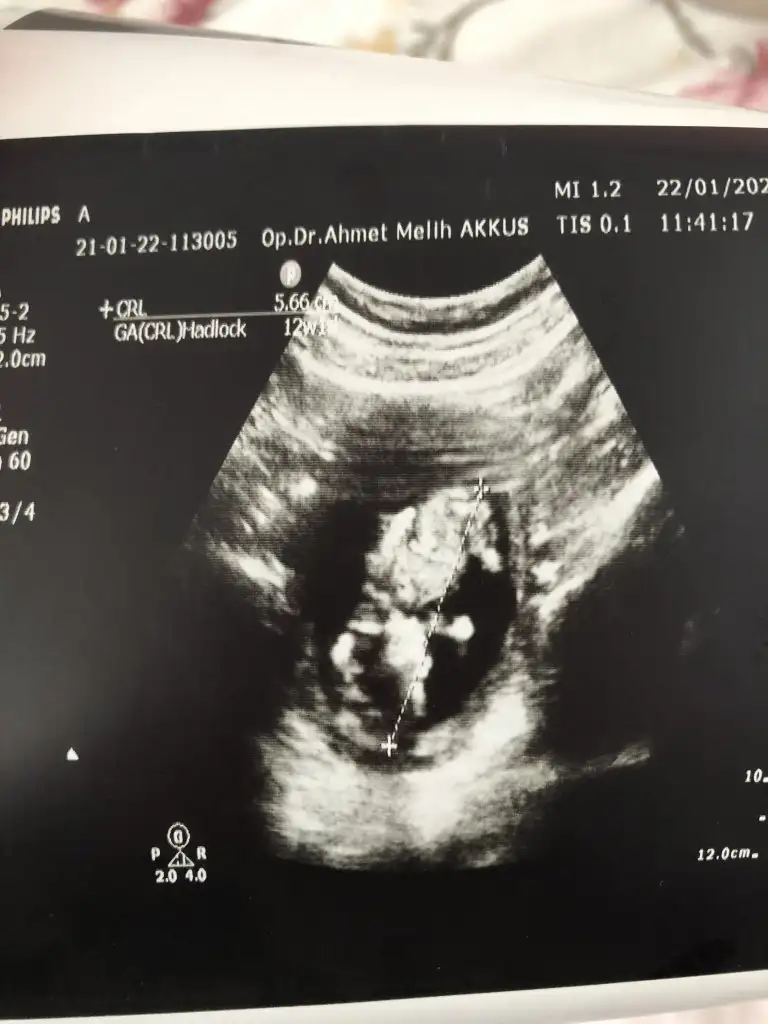

Merhaba Ikra meyra Ikra meyra bugun tekrar kontrol gittim atıyorum 12+2 🤗

• IMG_20210122_124028.webp

IMG_20210122_124028.webp

17,6 KB · Görüntüleme: 83

• IMG_20210122_124005.webp

IMG_20210122_124005.webp

26,3 KB · Görüntüleme: 84